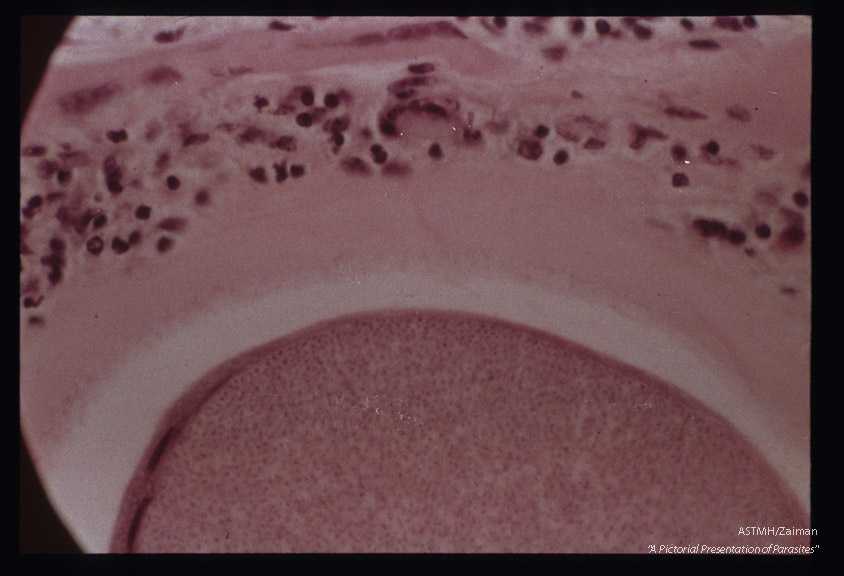

Cysts in striated muscle of reindeer.

Description: Cysts in striated muscle of reindeer.